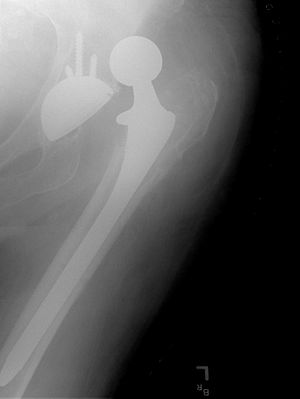

Cement free implant 16 days after surgery. Femoral component is cobalt chromium combined with titanium which induces bone growth into the implant. Ceramic head. Acetabular cup coated with bone growth inducing material and held temporarily in place with a single screw.